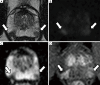

In recent years, active surveillance has been increasingly adopted as a conservative management approach to low and sometimes intermediate risk prostate cancer, to avoid or delay treatment until there is evidence of higher risk disease. A number of studies have investigated the role of multiparametric magnetic resonance imaging (mpMRI) in this setting. MpMRI refers to the use of multiple MRI sequences (T2-weighted anatomical and functional imaging which can include diffusion-weighted imaging, dynamic contrast enhanced imaging, spectroscopy). Each of the parameters investigates different aspects of the prostate gland (anatomy, cellularity, vascularity, etc.). In addition to a qualitative assessment, the radiologist can also extrapolate quantitative imaging biomarkers from these sequences, for example the apparent diffusion coefficient from diffusion-weighted imaging. There are many different types of articles (e.g., reviews, commentaries, consensus meetings, etc.) that address the use of mpMRI in men on active surveillance for prostate cancer. In this paper, we compare original articles that investigate the role of the different mpMRI sequences in men on active surveillance for prostate cancer, in order to discuss the relative utility of the different sequences, and combinations of sequences. We searched MEDLINE/PubMed for manuscripts published from inception to 1st December 2017. The search terms used were (prostate cancer or prostate adenocarcinoma or prostatic carcinoma or prostate carcinoma or prostatic adenocarcinoma) and (MRI or NMR or magnetic resonance imaging or mpMRI or multiparametric MRI) and active surveillance. Overall, 425 publications were found. All abstracts were reviewed to identify papers with original data. Twenty-five papers were analysed and summarised. Some papers based their analysis only on one mpMRI sequence, while others assessed two or more. The evidence from this review suggests that qualitative assessments and quantitative data from different mpMRI sequences hold promise in the management of men on active surveillance for prostate cancer. Both qualitative and quantitative approaches should be considered when assessing mpMRI of the prostate. There is a need for robust studies assessing the relative utility of different combinations of sequences in a systematic manner to determine the most efficient use of mpMRI in men on active surveillance.